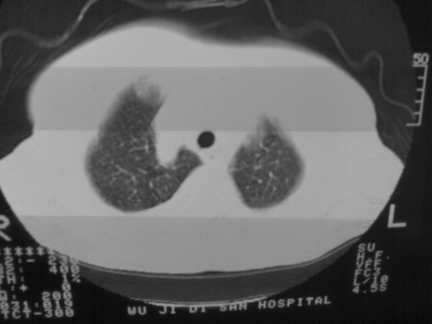

标题: CT13142:女 80 胸闷、气短、1w [打印本页]

标题: CT13142:女 80 胸闷、气短、1w

双侧胸腔积液

左室为主的心脏增大。

右肺感染;双侧胸腔少量积液,心影增大,可能与心功不全有关;胸内甲状腺肿。

右肺炎性变,双侧甲状腺肿,胸膜肥厚,心影增大考虑心功能不全.

胸内甲状腺肿;右肺中叶感染;双侧胸腔少量积液;心影增大,考虑有心功能不全。